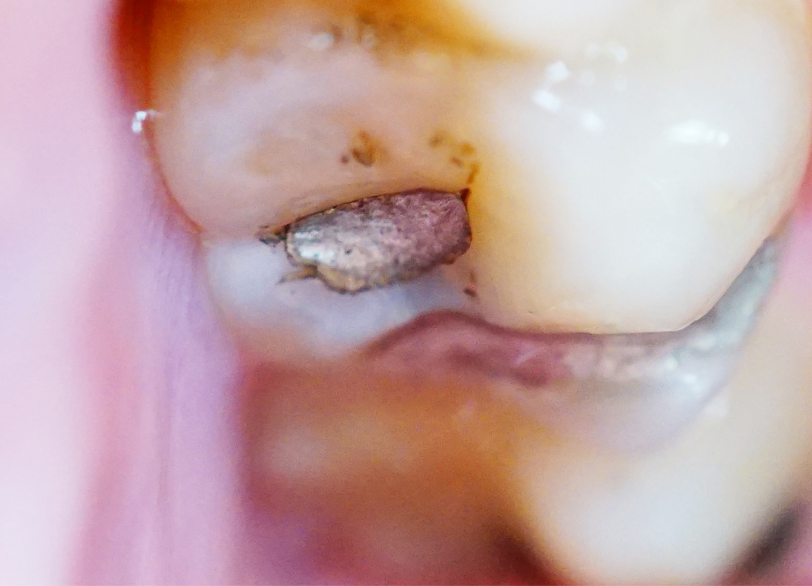

アマルガムと水銀の問題

アマルガムはかつて虫歯治療に広く使われていた詰め物で、その成分の約半分が水銀です。

水銀が人体にとって有害な物質であることは、広く知られています。

お口の中のアマルガムは食事の際の摩擦熱などによって、ごく微量の水銀蒸気を発生させると考えられています。

これが長年にわたって、無自覚のうちに体内に吸収され、蓄積していく可能性があるのです。

当院の安全なアマルガム除去

当院ではお口の中のアマルガムが、全身の健康に及ぼす影響を考慮し、その除去を推奨しています。

しかし、除去の際にアマルガムを削ることで、高濃度の水銀蒸気が発生します。

これを患者様や、術者が吸い込んでしまうことのないよう、当院では安全面に配慮した、特別なプロトコルに則って、除去作業を行っています。

安全な除去プロトコル

- ラバーダムの使用

治療する歯以外をゴムのシートで覆い、削りカスや金属片がお口の中に飛散したり、飲み込んだりするのを防ぎます - 口腔外バキュームの使用

強力な吸引力を持つバキュームを患者様のお口の外に設置し、治療中に発生する目に見えない金属の粉塵や、水銀蒸気を瞬時に吸い取ります - 術者・患者様の防護

術者は防毒マスクを着用し、患者様にもお顔を覆うガウンを着用していただくなど、万全の体制で臨みます